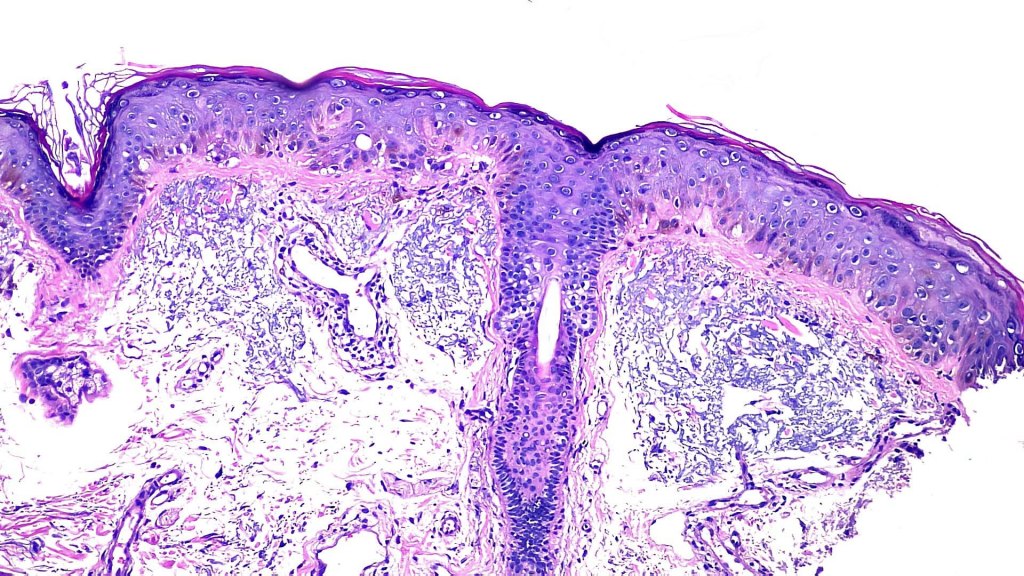

Histological features

•The epidermis is of normal thickness or less often acanthotic and lacks the lentiginous hyperplasia seen in actinic lentigo

•Hyperkeratosis but no parakeratosis

•Often pigmented but may be achromic

•Keratinocytes are enlarged & contain uniform, often vertically orientated, oval nuclei up to twice the size of uninvolved ones

•Absence of cytological atypia or mitoses above the basal layer

•Melanocytes may be present in increased numbers